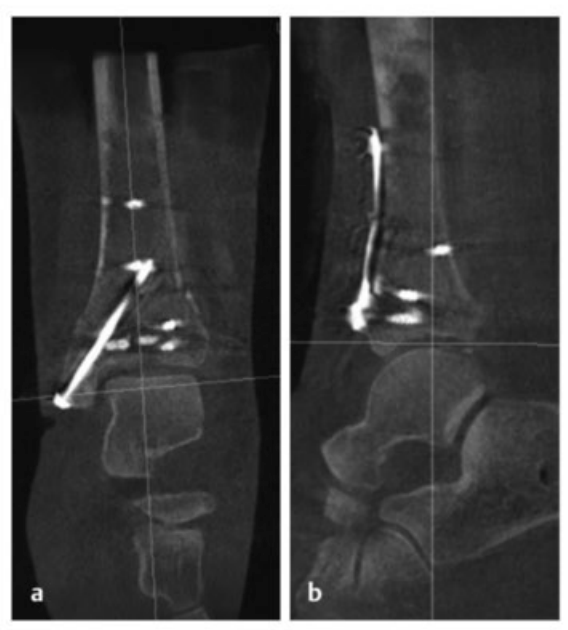

病例1在受伤后送往医院急诊,首先进行了跨踝关节外固定架。尽管患者初始存在Ⅱ度闭合性软组织损伤,但由于及时进行了复位并植入外固定架,未需实施筋膜间室切开术。在术前CT图像中,可清晰观察到3个主要骨折块及1个中央粉碎区。通过及时植入外固定架,可恢复关节位置,并有效避免软组织损伤进一步加重。

待软组织状况改善(出现 “皮肤皱纹征”)后,开始对患者进行手术治疗,首先处理腓骨(遵循 “先处理腓骨” 原则)。术中检查发现韧带联合存在不稳定情况。

术中三维CT 扫描确认骨折达到解剖复位,内植物位置良好。术后影像学检查证实骨折解剖复位,内植物位置正常。患者术后恢复过程顺利,关节功能恢复良好。